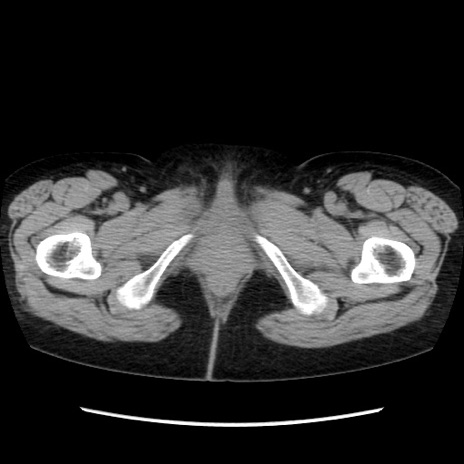

症例32(横断像)

【症例】40歳代 女性

【主訴】上腹部痛、嘔気・嘔吐

【現病歴】約9時間前頃から急に上腹部痛、嘔気、嘔吐が出現。改善しないため救急要請。

【既往歴】子宮頚癌(広汎子宮全摘術、放射線療法)、腸閉塞

【身体所見】腹部:平坦、軟、腸雑音亢進、上腹部を中心に腹部全体に圧痛あり。

【データ】WBC 8400、CRP 0.03